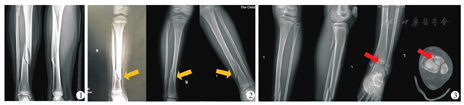

9例患儿除3例为腓骨青枝骨折外,6例患儿均为腓骨近端斜形骨折,骨折线由外上斜向内下,前高后低,均有不同程度的分离、侧方及短缩移位(图1)。9例病例胫骨骨折线在正位X线片上均为外上斜向内下(图2)。8例为胫骨下1/3骨干骨折,1例为胫骨下1/3骨折合并远端Tillaux骨折,无一例出现下胫腓分离(图3)。

成人Maisonneuve骨折一般为运动损伤,本研究发现,儿童胫骨下段骨折合并腓骨近端骨折除运动损伤(6/9)外,交通事故(3/9)也是一大致伤原因。成人Maisonneuve骨折依据Lauge-Hansen(LH)分型多将其归类为旋前外旋型损伤[7]。本组病例有以下影像特点可证实外旋暴力为致伤原因:①除3例腓骨青枝骨折外,有6例腓骨骨折线在侧位X线片显示为前上到后下,在正位X线片显示为外上到内下,腓骨骨折线的走行与成人旋前外旋型损伤腓骨骨折线走行一致;②侧位X线片上可见腓骨骨折端前后轻度分离;③有1例合并胫骨远端Tillaux骨折,该骨折普遍被认为是外旋暴力引起[8]。因此,可以认为在下肢受到外旋暴力导致儿童胫骨下段骨折后,腓骨受骨间膜牵拉引起高位腓骨骨折。胫骨骨折线在X线片上可表现为斜形(6例)或螺旋形(3例),但总体走行均是外上到内下。这也提示临床上发现扭伤致胫骨下段外上到内下的斜形或螺旋形骨折时,应当考虑合并腓骨近端骨折的可能。此外本组9例均未出现下胫腓解剖关系的异常,同时5例采取手术治疗的患儿在复位胫骨后,其腓骨分离与短缩移位均有明显改善,说明下胫腓在外伤后仍是一个整体,进一步证实这类患儿未出现严重的下胫腓联合韧带或骨间膜的撕裂。